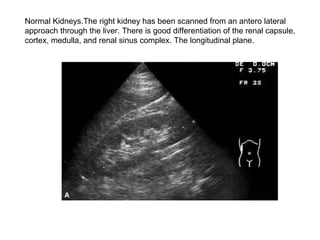

Normal Kidneys.The right kidney has been scanned from an antero lateral  approach through the liver. There is good differentiation of the renal capsule, cortex, medulla, and renal sinus complex. The longitudinal plane.

The transverse plane.